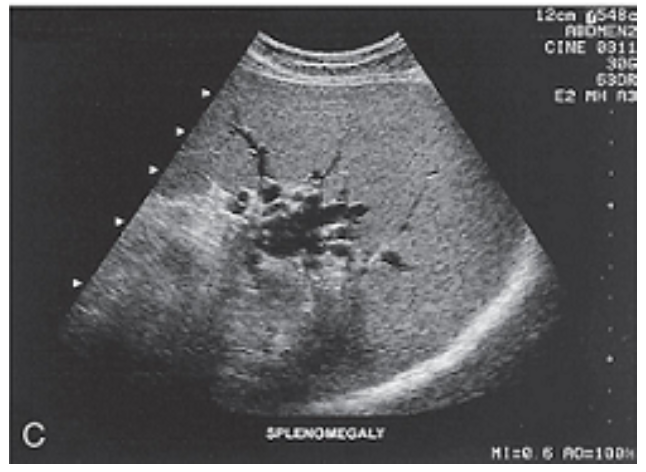

Splenomegaly: The dilated splenic hilum is secondary to portal hypertension, with hepatosplenomegaly.